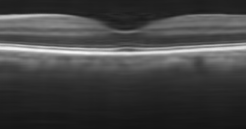

The effect of the overlap of the patches on the final output of the algorithm has been investigated in the next simulation. For this purpose, the outputs of the proposed approach for the situations and have been compared. When , the patches have no overlap. The resulting higher resolution OCT images for each situation have been illustrated in Fig. 8. Visual comparison in addition to the PSNR and SSIM for each image, show that using patches with overlap, we can increase the performance of the algorithm and consequently improve the quality of the output image.

Reference image

Using patches without overlap

Using patches with overlap